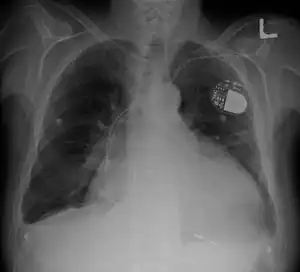

Cardiomegaly on chest X-ray with a pacemaker

• Pacemaker: Coordinates the contractions between the left and right ventricle. In people who may be at risk of serious arrhythmias, drug therapy or an implantable cardioverter-defibrillator (ICD) may be used.

• ICDs: Small devices implanted in the chest to constantly monitor the heart rhythm and deliver electrical shocks when needed to control abnormal, rapid heartbeats. The devices can also work as pacemakers.